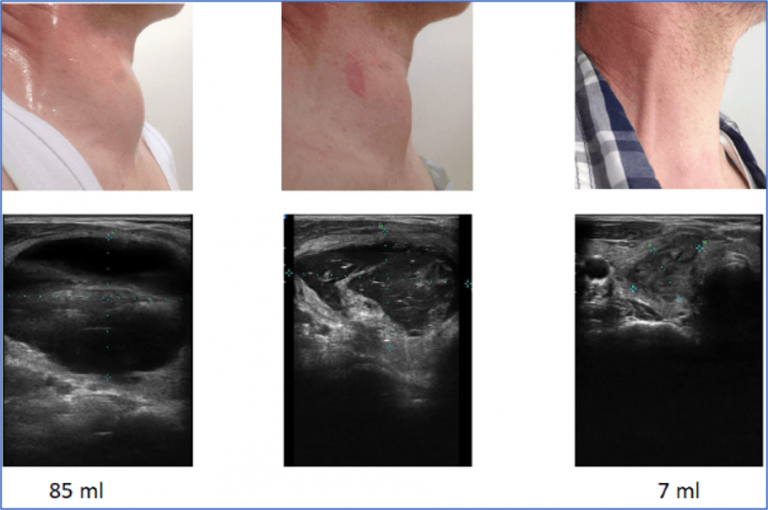

Unter einer Schilddrüsenzyste versteht man einen mit Flüssigkeit gefüllten Hohlraum in der Schilddrüse, der von einer epithelialen Hülle umgeben ist Wenn Sie zu den Menschen gehören, die nur wenig ihren Körper kennen oder mal untersuchen, dann fällt die Zyste nur selten auf. Es muss klargestellt werden, dass die wahre Zyste der Drüse in der klinischen Praxis äußerst selten ist, meist als Sekundarstufe vor dem Hintergrund einer sich bereits entwickelnden Onkopathologie.

Illustrationen Schilddrüsenzellen MedicalGraphics. Eine Schilddrüsenzyste ist eine flüssigkeitsgefüllte Struktur innerhalb der Schilddrüse, die sich im Halsbereich befindet Liegen mehr als vier Schilddrüsenzysten in der Schilddrüse vor, spricht man von einer polyzystischen Schilddrüsenerkrankung.Schilddrüsenzysten sind häufig, etwa 3-5% der Weltbevölkerung haben eine oder mehrere.